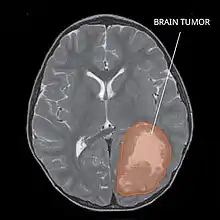

| Primitive neuroectodermal tumor of the central nervous system in a 5-year-old |

A central nervous system primitive neuroectodermal tumor, often abbreviated as PNET, supratentorial PNET, or CNS-PNET,[1] is one of the 3 types of embryonal central nervous system tumors (medulloblastoma, atypical teratoid rhabdoid tumor, and PNET).[2] It is considered an embryonal tumor because it arises from cells partially differentiated or still undifferentiated from birth.[1] Those cells are usually neuroepithelial cells,[1][2][3] stem cells destined to turn into glia or neurons.[4] It can occur anywhere within the spinal cord and cerebrum and can have multiple sites of origins, with a high probability of metastasis through cerebrospinal fluid (CSF).[1][2]

PNET has five subtypes of tumors: neuroblastoma, ganglioneuroblastoma, medulloepithelioma, ependymoblastoma, and not otherwise specified PNET.[1] It is similar to medulloblastoma regarding histology but different regarding genetic factors and tumor site. It is a rare disease occurring mostly among children,[1][2] accounting for 1.9 to 7% of childhood brain tumors.[2] Symptoms involve emotional, visual, motor, and speech defects.[2] Magnetic resonance imaging (MRI) and computed tomography (CT) are used to diagnose PNETs.[2] Even though a universal treatment plan hasn't been stablished yet, common strategies involve chemotherapy and radiotherapy for individuals older than 3 years of age.[1][2] Their efficacy, however, is still controversial.[2] Surgery can be used to remove mass affected by tumorous cells.[2] The prognosis of the disease is more positive for adults than for children, who have a higher probability of having sequelae from the tumor.[1][2]